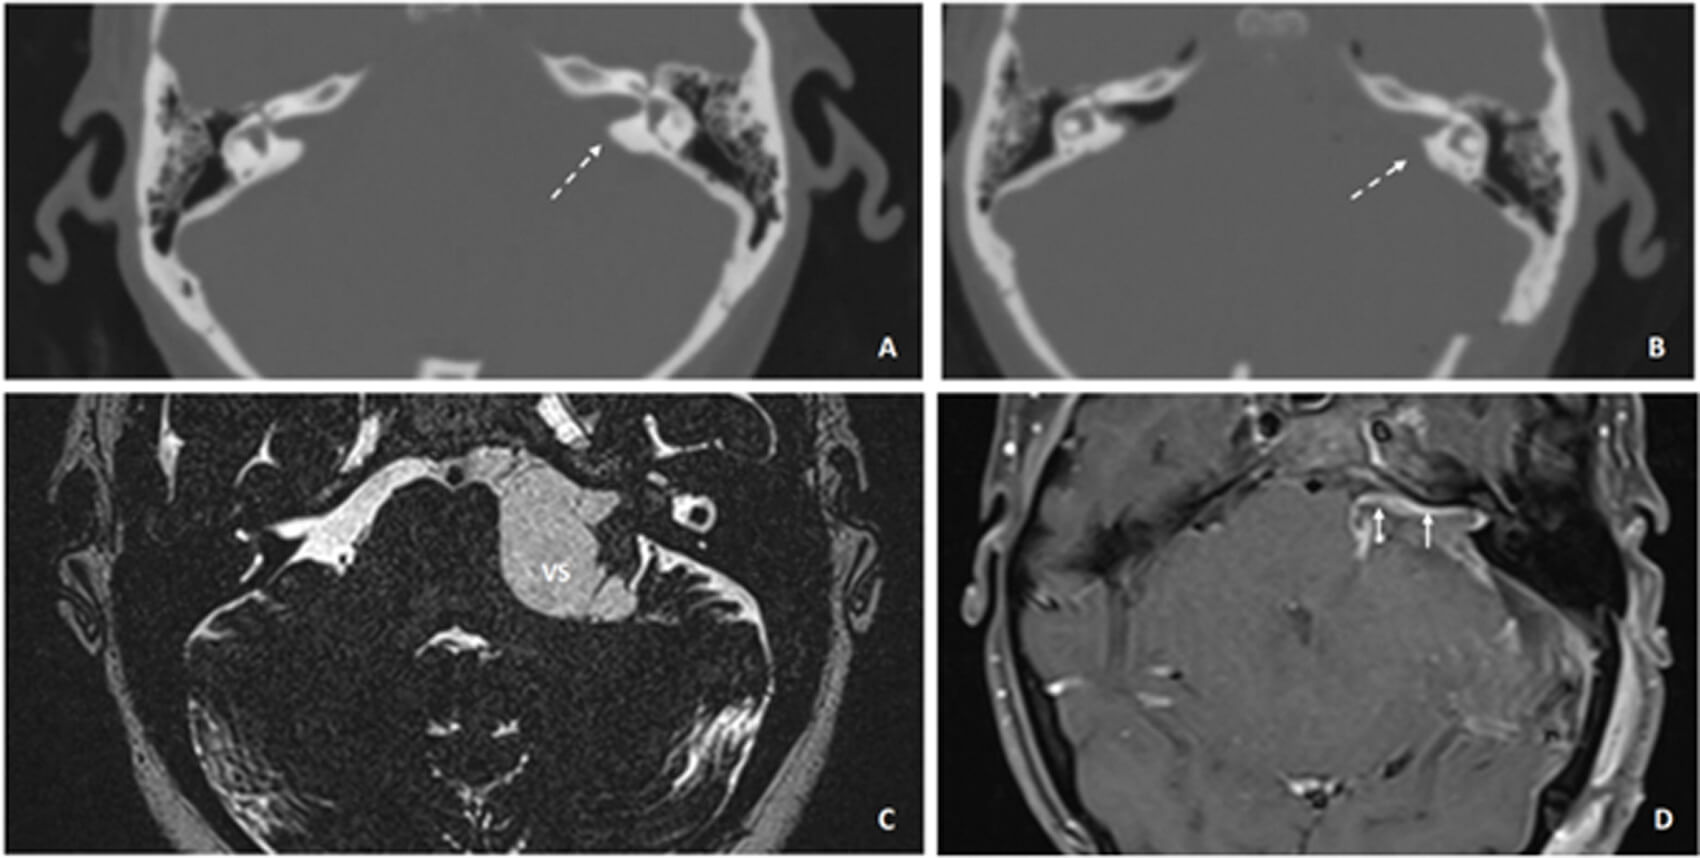

Figure 2: Preoperative computed tomography (CT) of the temporal bones: A) of a patient with a large left VS; and B) the postoperative scan showing the area of the bone of the IAM that has been removed, highlighted with dashed arrows. C) The magnetic resonance imaging T2-weighted steady state shows the large VS preoperatively; and D) postoperatively (day three) on post-gadolinium T1-weighted MRI. The short arrows highlight the postoperative enhancement along the whole route of the facial nerve.